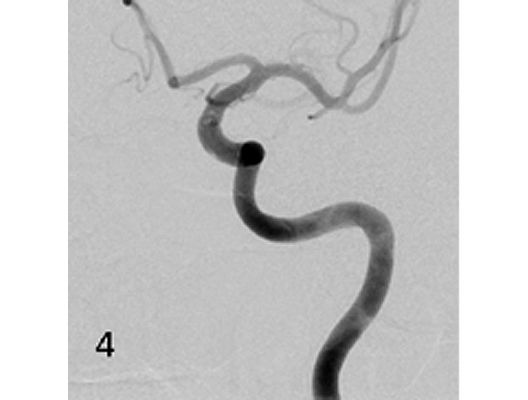

Angiographie: Behandlung von Aneurysmen

Behandlung von Aneurysmen

Aneurysmen an der Gefäßen des Gehirns können in vielen Fällen minimalinvasiv durch einen Zugang durch das Gefäßsystem, zumeist von der Leiste aus behandelt werden (sog. Endovaskuläre Therapie). Dabei gibt es z.B. die Möglichkeit ein Aneurysma durch Einbringung von Platinspiralen zu verschließen (sog. Coiling). Auch für komplexe Aneurysmen stehen inzwischen verschiedene endovaskuläre Methoden zur Verfügung.

Das Beispiel zeigt die angiographischen Bilder einer Patientin, bei der es zu einer Sehstörung gekommen war. Die Ursache war ein großes Aneurysma der Halsschlagader an der Schädelbasis (Bild 1). Bild 2 zeigt die Lage des Aneurysmas hinter dem Auge. Durch den Druck des Aneurysmas auf den Sehnerv war es zu der Sehstörung gekommen. Die Patientin wurde mit einer speziellen Gefäßprothese versorgt, welche über eine Punktion der Leistenarterie in die Halsschlagader eingesetzt wurde (Bild 3). Bei der Kontrolle nach 6 Monaten zeigte sich ein vollständiger Verschluss des Aneurysmas (Bild 4). Die Sehstörung hatte sich vollständig zurückgebildet.